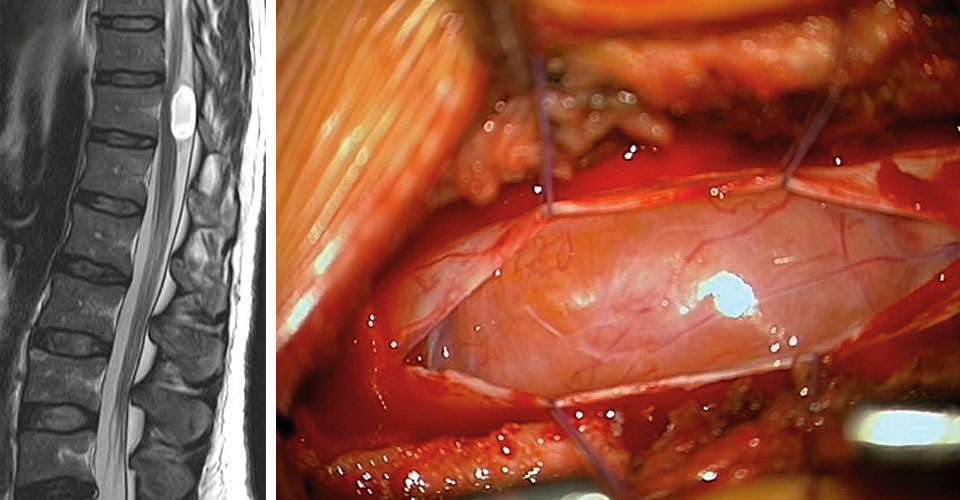

Fall 4

Ein 82-Jähriger kam mit Sensibilitätsstörungen an beiden Händen, Gangunsicherheit und einer ungerichteten Fallneigung bei geschlossenen Augen in die Klinik. Die Magnetresonanztomographie zeigte eine intramedulläre Raumforderung auf Höhe HWK 3/4. Die Histologie nach Resektion brachte ein melanotisches Schwannom ans Licht. Dieser extrem seltene Subtyp birgt ein 10%iges Malignisierungs- und Metastasierungspotenzial und bedarf deshalb nach der Entfernung einer MRT-Kontrolle. Spätestens beim Rezidiv ist eine Radiatio angezeigt.